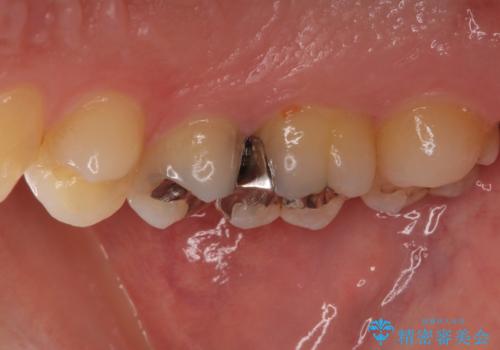

- 奥歯の銀歯の下にあるむし歯治療を希望して来院された患者様です。

口を開けたときに見えてしまう部分はセラミックインレーやジルコニアクラウンに、目立たない部分はゴールドインレーにてむし歯治療を行うこととしました。

機能面を優先すると、PGAインレー(ゴールドインレー)による修復治療やPGAクラウンによる補綴治療が望ましいのですが、笑ったときに見えている銀歯がどうしても気なってしまうとのことで、目立ってしまう奥歯はセラミックインレーやセラミッククラウンを装着することとしました。